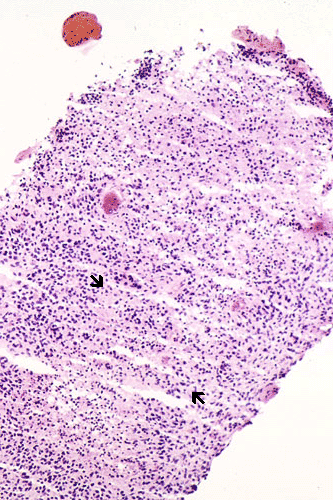

On low-magnification, a streak of pale staining suspicious of necrosis is present and is confirmed at higher magnification. The necrotic streak is delimited by arrows.